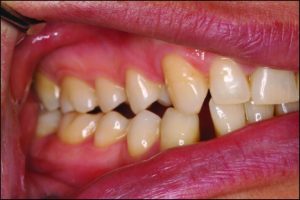

Occlusal discrepancies negatively affect the success of the prosthesis. In partially edentulous cases, due to reasons such as loss of teeth at different times or prolonged edentulism, the remaining teeth tend to tip, drift, or supra-erupt into the edentulous spaces (Figure 9-6).

Figure 9-6. In a patient who has been edentulous for a long time, positional changes in the natural teeth lead to occlusal discrepancies.